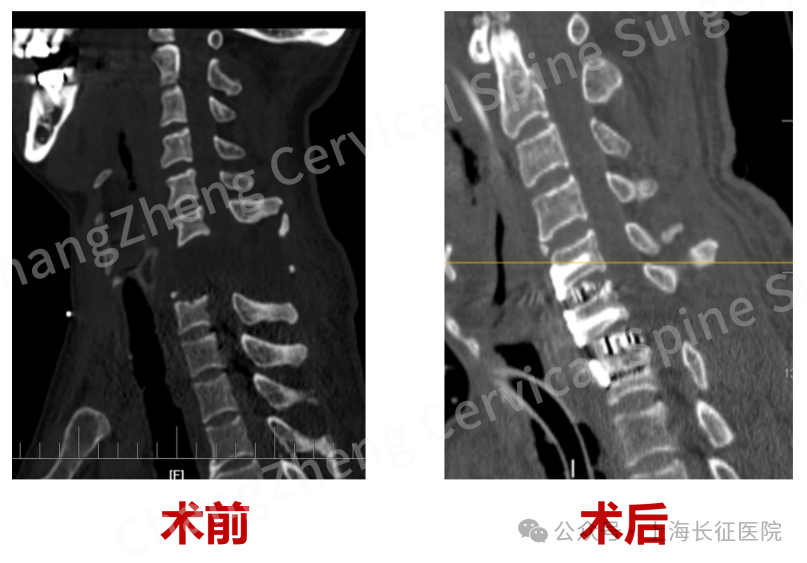

影像学检查结果更令人震惊:颈椎发生极其罕见的大跨度脱位,其严重程度犹如“身首离断”,已造成脊髓严重挫伤、关键神经血管结构撕裂。

在患者极其脆弱的生命体征监护下,专家们凭借炉火纯青的解剖功底和显微操作技术,小心翼翼地清除巨大血肿,克服严重粘连和畸形,最终精准地将完全离断错位的颈椎结构完美复位。

尤为关键的是,团队创新性地应用了“卫星钢板”固定技术,在常规固定之外巧妙增加辅助钢板,为重建的颈椎提供了前所未有的超强稳定性,这一技术应用在此类极端病例中尚属首创。